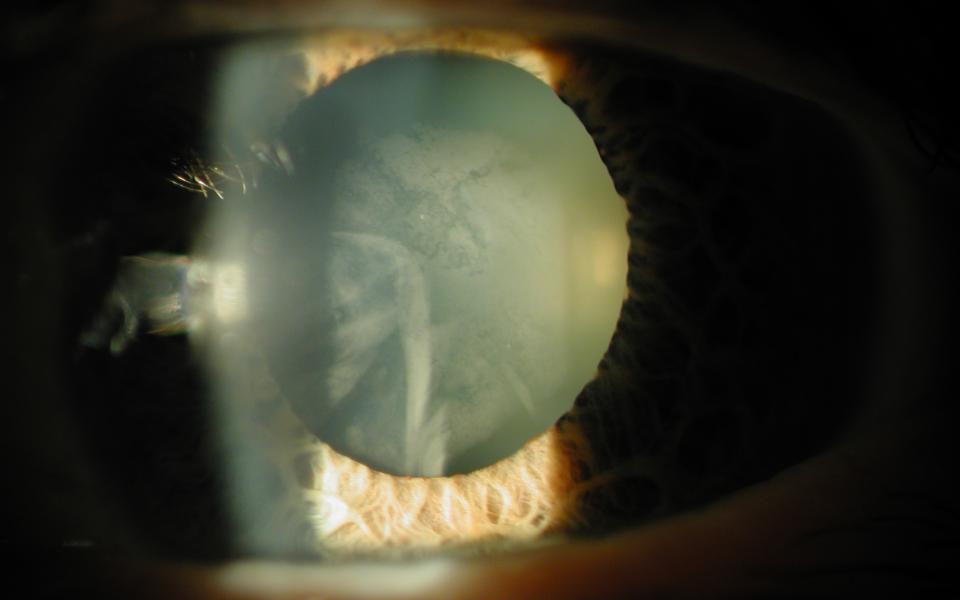

The Argentinan Flag sign more commonly occurs in patients with mature nuclear sclerosis. The anterior capsule is stained with trypan blue (Vison Blue). When the capsule is decompressed with a 25G